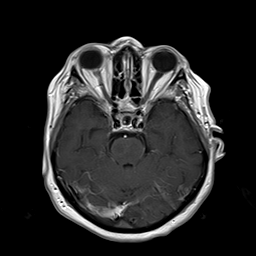

(a) Guide 𝑮𝑮\boldsymbol{G}

Refer to caption

(b) Input 𝑰𝑰\boldsymbol{I}

(c) Guidance map 𝑴𝑴\boldsymbol{M}

(d) Prediction 𝑷𝑷\boldsymbol{P}

(e) Ground truth

Figure 2: Inputs and outputs of the guided filtering pipeline based on the WDSR network. T1 & T2 MRI pairs (a)-(e) and CT & MRI projection images (f)-(j).